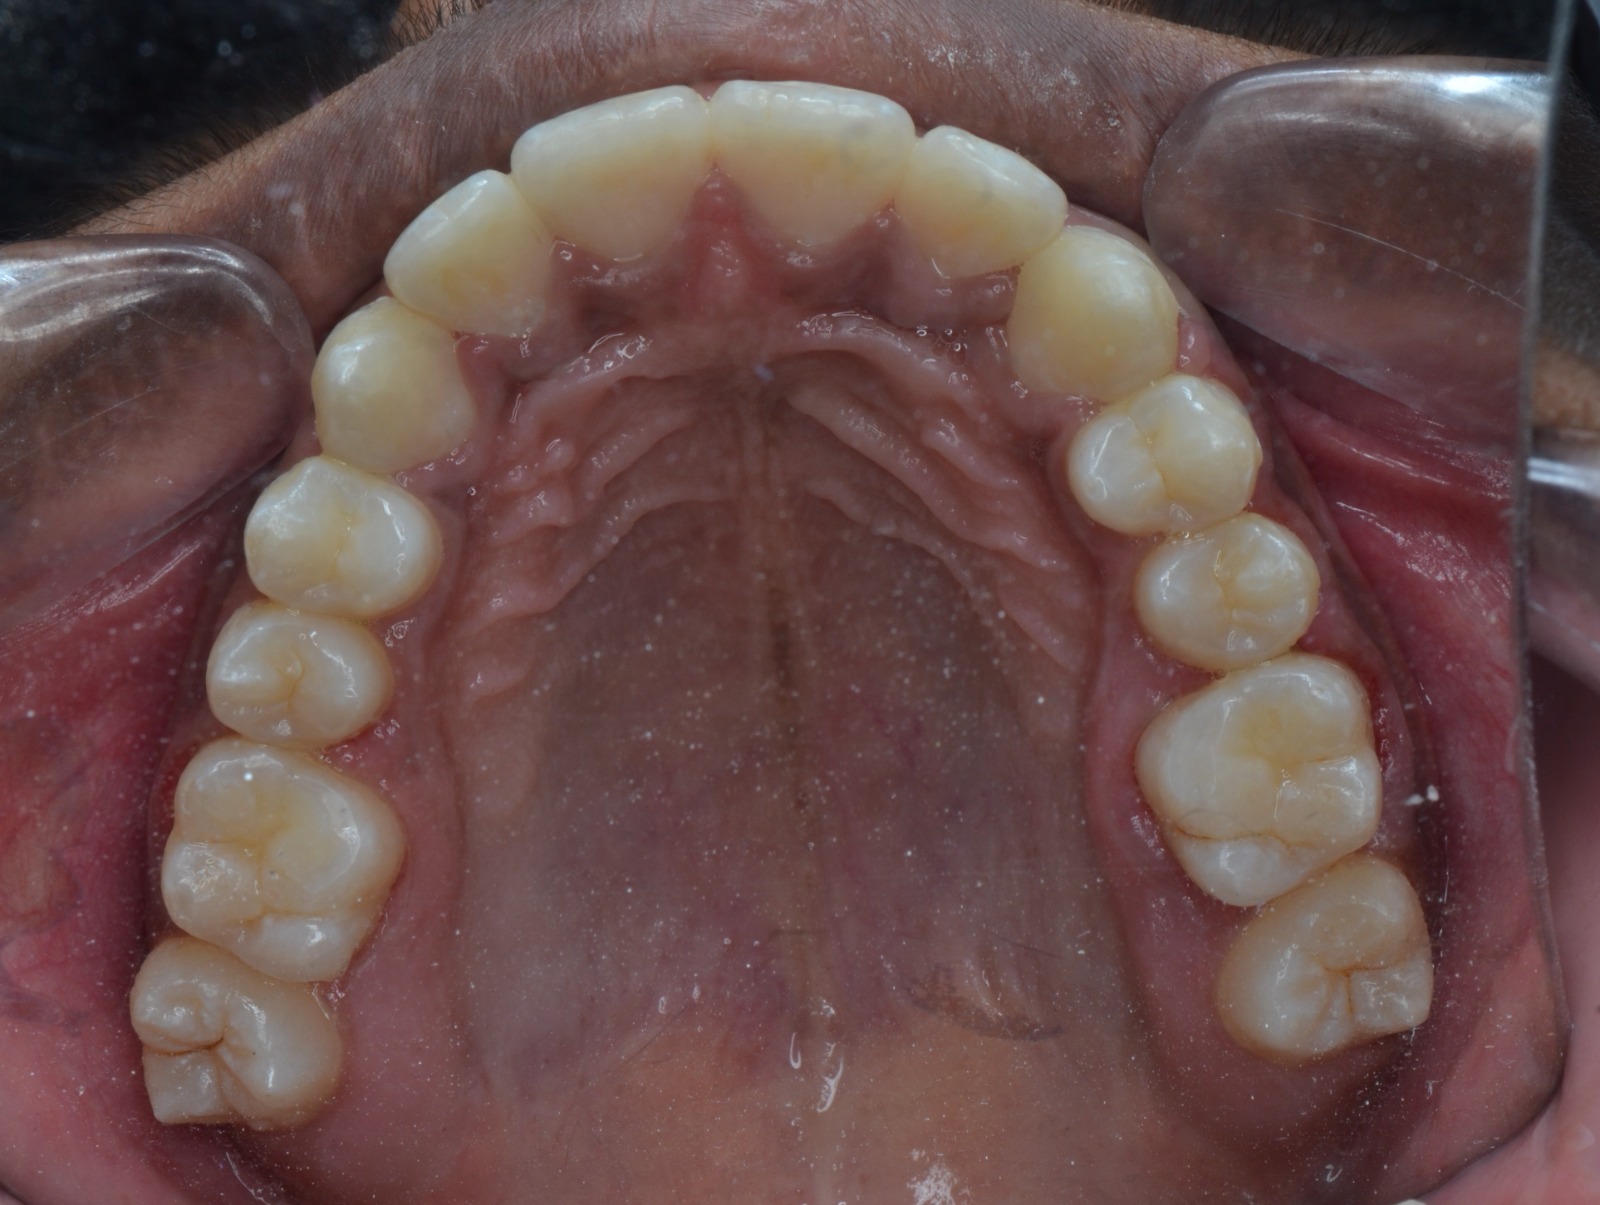

After/Before

See stunning smile transformation before and after

Before After